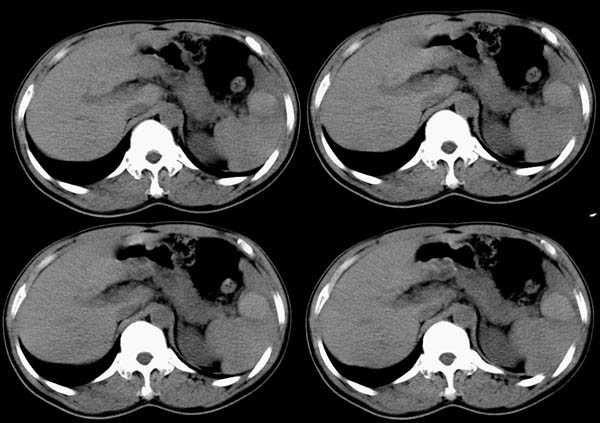

m50y以腹疼、腹胀2小时就诊。腹透肠胀气较明显,余无明显异常。做ct时腹疼已明显缓解;病人否认外伤史,否认血液病变、否认肝炎史。建议第二天做ct增强,病人第二天放弃了增强。脾脏区较高密度影ct值为60hu,正常脾脏ct值为45hu(窗宽:150,窗位:56)。

脾区病变局部2mm重建:

ct表现:脾脏内见较高密度影ct值为60hu,正常脾脏ct值为45hu(窗宽:150,窗位:56)。 边界清晰,周围见略低密度影

脾脏实质内高密度病变,ct值为60hu,边界清晰,无明显外伤病史,腹痛、腹胀2小时就诊,首先考虑脾脏血管瘤破裂出血。